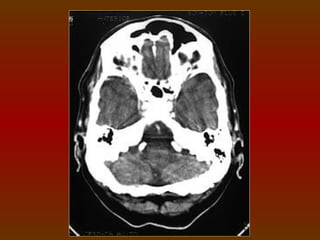

CORTE 2

a) Globo ocular

b) Nervo óptico

c) Lobo temporal

d) Osso petroso temporal

e) Cerebelo

f) Seio esfenoidal

g) Musculatura ocular